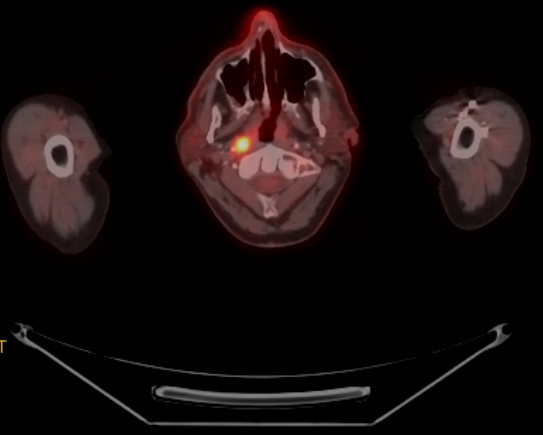

4. 4. 영상 검사